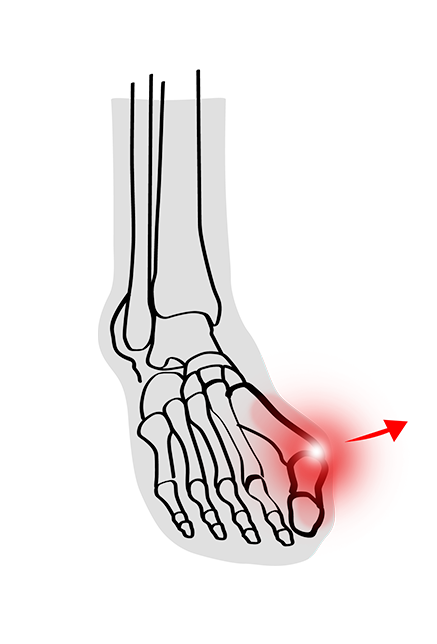

Ever wondered what that bony lump on the side of your foot is? Chances are it's a Bunion. Bunions are relatively harmless and thankfully do not usually require any medical intervention. However, when left to their own devices, they can cause heaps of pain and discomfort, drastically impacting your quality of life.